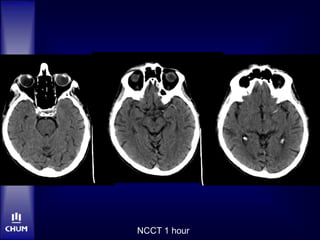

NCCT 1 hour

Case 2 – Mr. RD

NCCT

 L eye deviation, L HMCA

 ASPECTS 10

CTA not done…

 Obvious HMCA

 Disabling NIHSS

 Avoid delays to Angio (NCCT already done)